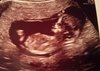

Zobacz załącznik 842481

Obiecałam zdjęciatutaj był szok z długich nóg mojego modela/modelki

gwarantuje, że to po ojcu hih

to zdjęcie zrobiło mi dzień, jest świetne